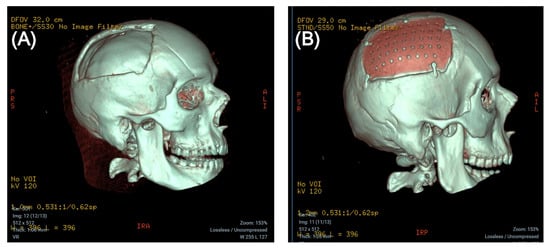

The patient thus received a custom-made CP implant made of polyether ether ketone (PEEK), MEDPRIN (https://www.medprin.com/, accessed on 11 January 2024) (See Figure 3).

Figure 3. Three-dimensional CT scan before (A) and after (B) cranioplasty.